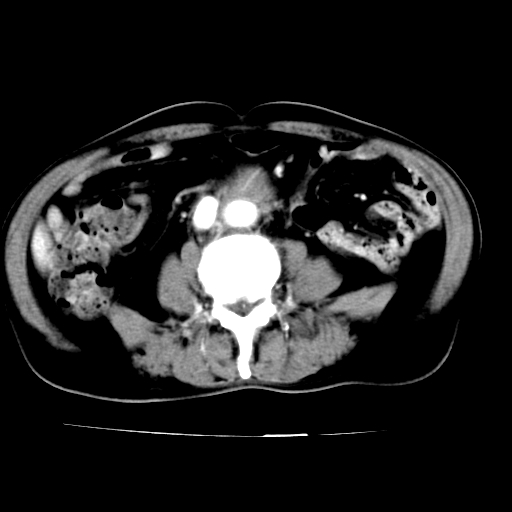

标题: V0243:右髂总动脉瘤附壁血栓形成?破裂?动静脉瘘? [打印本页]

标题: V0243:右髂总动脉瘤附壁血栓形成?破裂?动静脉瘘?

男,75岁,腹痛月余,彩超发现脐周腹主动脉异常回声。临床诊断:腹主动脉瘤。

ct诊断:右骼总动脉囊性动脉瘤并瘤内附壁血栓形成,与下腔静脉之间形成动静脉瘘。

请问各位老师:能排除动脉瘤破裂的可能吗?